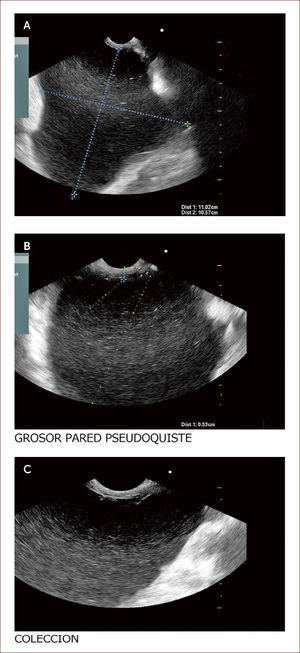

Paciente con seudoquistre del páncreas posterior a cuadro de pancreatitis aguda. La paciente tuvo dolores que no fueron rotulados como tal y los manejaron en el campo (Fundo), como algo digestivo. Al consultar en la capital a una clínica encuentran en la TAC esta lesión. En la imagen A se ve la medición del tamaño del quiste y en la imagen B el grosor de la pared de 6mm. En la C a la izquierda el contenido líquido con pocos detritus. Fue llevada a drenaje y colocacion de stent.

Los seudoquistes se presentan como una complicación de la pancreatitis y aparecen luego de seis semanas de evolución de la enfermedad. Estas colecciones son variables en cuanto a tamaño y su manejo depende de si hay síntomas o no. Si son muy sintomáticos, la endoscopia y el drenaje son la indicación primaria y el EUS es el mejor método diagnóstico, que acerca a las verdaderas características del quiste, pudiendo obtener datos de contenido, infección, ancho de la pared, componentes vasculares y por tanto, se disminuyen las complicaciones del drenaje por esta vía.